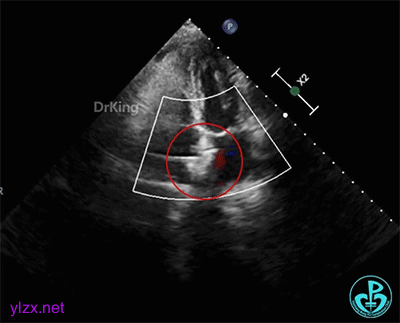

术前经食道超声描述:室间隔连续完整,房间隔中部菲薄,呈瘤样凸向右房面,基底宽约12mm,膨出约8mm。卵圆窝处薄弱,呈纤细线样回声,原发隔与继发隔间见纤细裂隙,入口约0.4mm,出口约0.8mm,卵圆瓣长约20.1mm,原发隔摆动幅度约13mm,继发隔厚约4.5mm,瓦式呼吸后,入口较宽约3.8mm,出口较宽约2.0mm,卵圆瓣左房侧末端迂曲。CDFI裂隙处可见微量左向右过隔血流信号。左心耳显示清楚,内未见异常回声。主动脉内中膜欠光滑,窦部宽约25mm,管腔未见明显狭窄与扩张,CDFI未见明显异常血流信号。各房室腔比例尚可,未见明显节段性室壁运动异常,各瓣膜形态、结构正常,启闭尚可。

经食道超声三维、二维和右心声学造影图像: